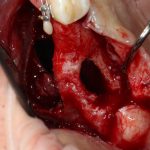

Итак, Зинаида на приеме.

Вот клиническая картина через 4 месяца после ранее проведенной имплантации с остеопластикой:

Как видишь, коллеги из недалекой дружественной страны не осилили снятие швов. Мне это не нравится, хотя и объясняет, почему люди готовы ехать за тыщи километров ради 20-минутной операции удаления зуба мудрости.

Ну хорошо. Швы сняли. Делаем разрез. Обрати внимание, что после всех проведенных операций у нас остается очень небольшой по ширине слой жевательной слизистой оболочки: